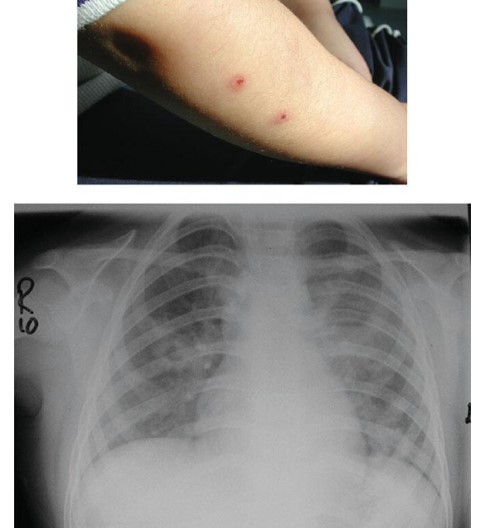

Common skin lesions:

Common skin rashes: